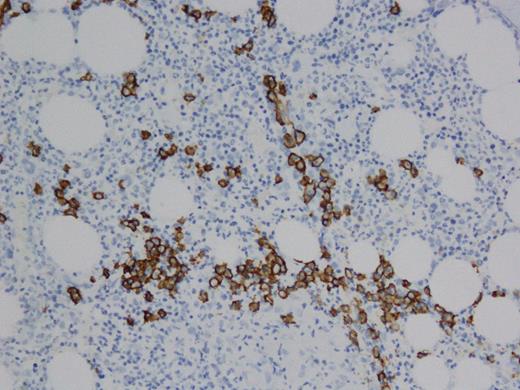

A 60 year old female with past medical history of stage IIA Hodgkin's lymphoma diagnosed in 1992, treated with total nodal radiation with recurrence in 1997 treated with 6 cycles of ABVD achieving complete remission. The patient was found to have hypercalcemia (11.0 mg/dL) and renal failure (1.29 mg/dL) in March 2011. Hypercalcemia workup revealed suppressed PTH (<3 pg/ml), elevated ionized calcium (6.1 mg/dL) elevated parathyroid related peptide (38pg/ml), normal vitamin D and ACE levels. Serum protein electrophoresis (SPEP) showed M-spike of 0.9 g/dL. Immunofixation electrophoresis (IFE) demonstrated an IgG monoclonal immunoglobulin without a corresponding light chain (figure 1). Free serum kappa and lamda light chains were within normal limits. Serum IgG was elevated (4678 mg/dL), normal IgA (127 mg/dL) and low IgM (39mg/dL). Also, Beta-2 microglobulin was elevated (14.3 mg/L). The patient was seen by hematology for monoclonal gammopathy and hypercalcemia and a solid tumor work up was recommended given that the most common the mechanism of hypercalcemia for multiple myeloma is osteoclast-driven and not PTHrP related. CT chest/abdomen/pelvis, bone scan, bone survey, mammography, pelvis ultrasound were negative. Bone marrow biopsy was performed November 2011 showing 10% plasma cells (PC) by CD138, non clonal by kappa/lambda. Patient was placed on zolendonic acid for hypercalcemia and her renal function and hypercalcemia continued to worsen over a period of months. A kidney biopsy was performed in April, 2012 and revealed acute and chronic tubulointerstitial nephritis with secondary glomerulosclerosis and mild interstitial fibrosis and tubular atrophy suggestive of sarcoidosis and the patient was placed on a course of prednisone with transient improvement in calcium and renal function. The patient presented in emergency room in April 2013 with altered mental status. She was found to have hypercalcemia (12.0 mg/dL), renal failure (1.55 mg/dL),). SPEP revealed M-spike 0.64 g/dl. IFE displayed a broad band of IgG heavy chain, without associated light chains and severe depression of the non-monoclonal IgG. Serum immunoglobulins demonstrated elevated IgG (2110 mg/dL), normal IgA (46 mg/dL) and decreased IgM (<21 mg/dL). Bone marrow biopsy showed 5% PCs (figure 2), non clonal by kappa/lambda- but exclusive for IgG by IHC, without any staining for IgA or IgM (figure 3). Cytogenetics were normal. Based on the constellation of findings and similarity to prior workup the patient was diagnosed with IgG heavy chain disease and therapy with cytoxan, dexamethasone, bortezomib was initiated. Calcium levels improved and she has recovered clinically; she is currently completing her second cycle of therapy. We plan to follow PTHrP levels along with routine paraprotein assessments.

Few PCs + kappa light chain by IHC. 3b. Few PCs + for lambda light chain by IHC 3c. Majority of PCs show + IgG by IHC. 3d. PCs - IgM by IHC.